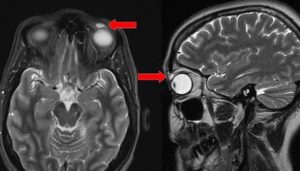

பிரிட்டனை சேர்ந்த பெண்(48) ஒருவர் கண்ணில் வீக்கம் ஏற்பட்டதால் சிகிச்சைக்காக மருத்துவமனையில் அனுமதிக்கப்பட்டார். அப்போது அவரது கண்ணை ஸ்கேன் செய்த மருத்துவர்கள் அதிர்ச்சியடைந்தனர். அவரது இடது கண்ணின் மேற்புறத்தில் சுமார் 8 மில்லி மீட்டர் அளவுடைய காண்டாக்ட் லென்ஸ் சிக்கியிருப்பதை ஸ்கேன் மூலம் மருத்துவர்கள் கண்டறிந்தனர்.

ஆனால், அந்த லென்ஸ் கீழே விழாமல் 28 ஆண்டுகளாக அவரது கண்ணின் மேற்புறத்தில் சிக்கி இருந்துள்ளது. வலி போன்ற எவ்வித அறிகுறிகளையும் ஏற்படுத்தாமல் இவ்வளவு ஆண்டுகளாக அவரது கண்ணிலேயே லென்ஸ் சிக்கி இருந்துள்ளது.